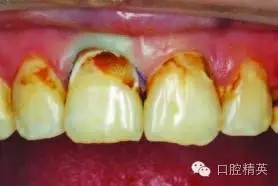

術(shù)前圖1a:患者主訴上前牙齲壞

患者主述上前牙齲壞(圖1a)?;颊叻裾J(rèn)不適癥狀,僅是因?yàn)榘l(fā)現(xiàn)其外觀變化了。

檢查發(fā)現(xiàn),上前牙有V類洞和III類洞得齲壞。